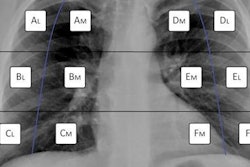

Weiss and colleagues wanted to test the potential of artificial intelligence (AI) in estimating 10-year cardiovascular risk from routine chest radiographs. They developed a deep learning model that was trained using 147,497 chest radiographs from 40,643 cancer screening trial participants and conducted independent testing in a separate cohort of 11,430 outpatients who were potentially eligible for intervention.